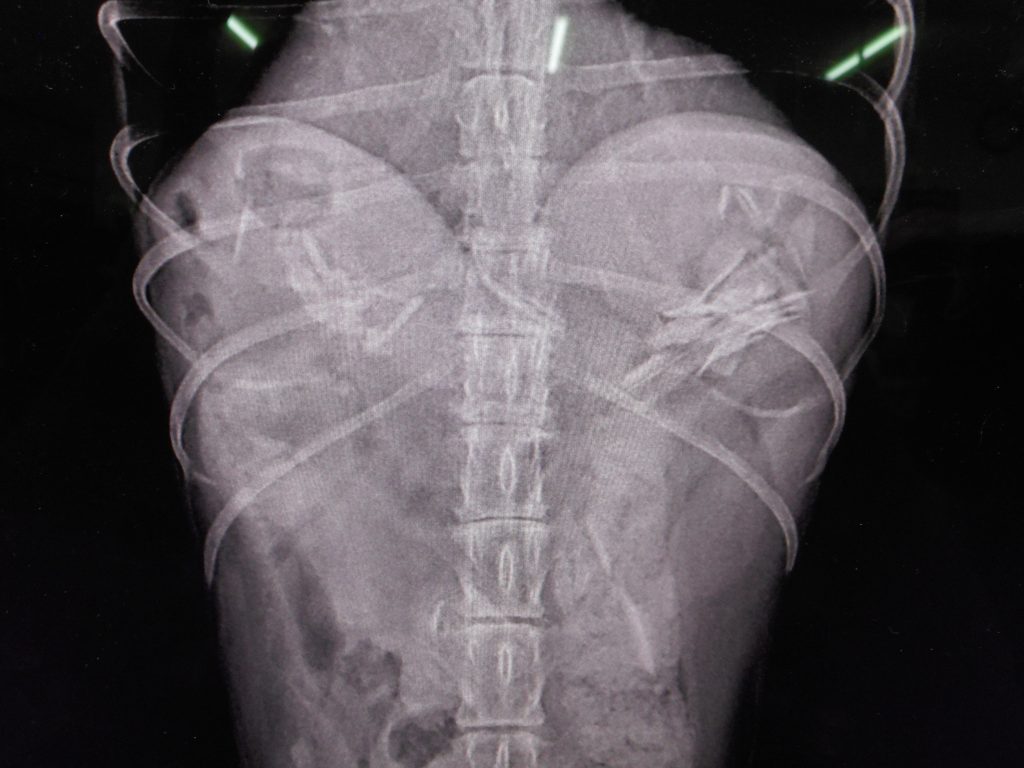

縦から診ると、

どこにあるか?

ココです